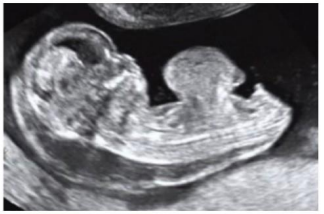

Uma paciente de 16 anos de idade, G1, realizou ultrassonografia morfológica de primeiro trimestre, na qual foi detectado um defeito de parede abdominal central ventral no feto, como mostra a imagem a seguir.